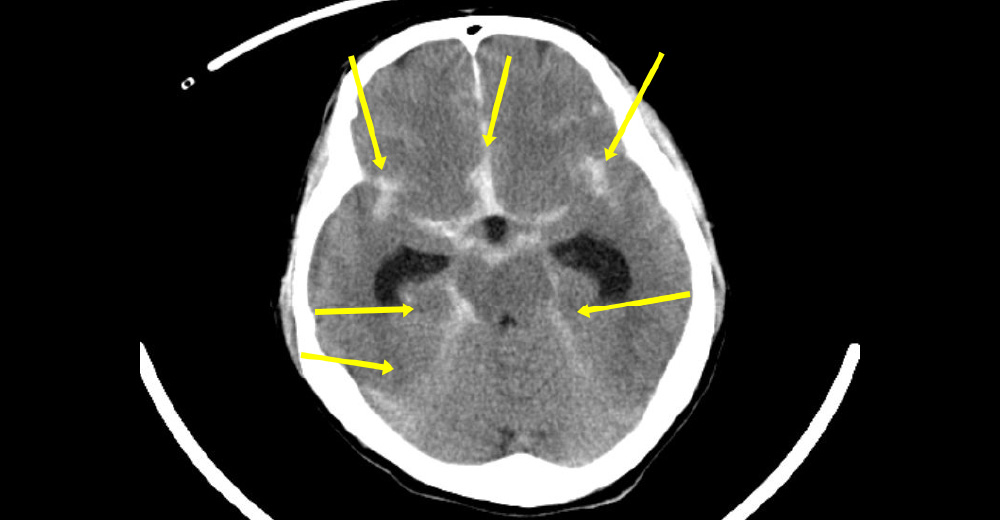

慢性硬膜下血腫

いつもとなんとなく様子がおかしい との御家族の指摘で、診断された、高齢者の慢性硬膜下血種の症例です。

緊急頭部CTで確定診断されました。 は出血、は脳が圧排されている所見です。